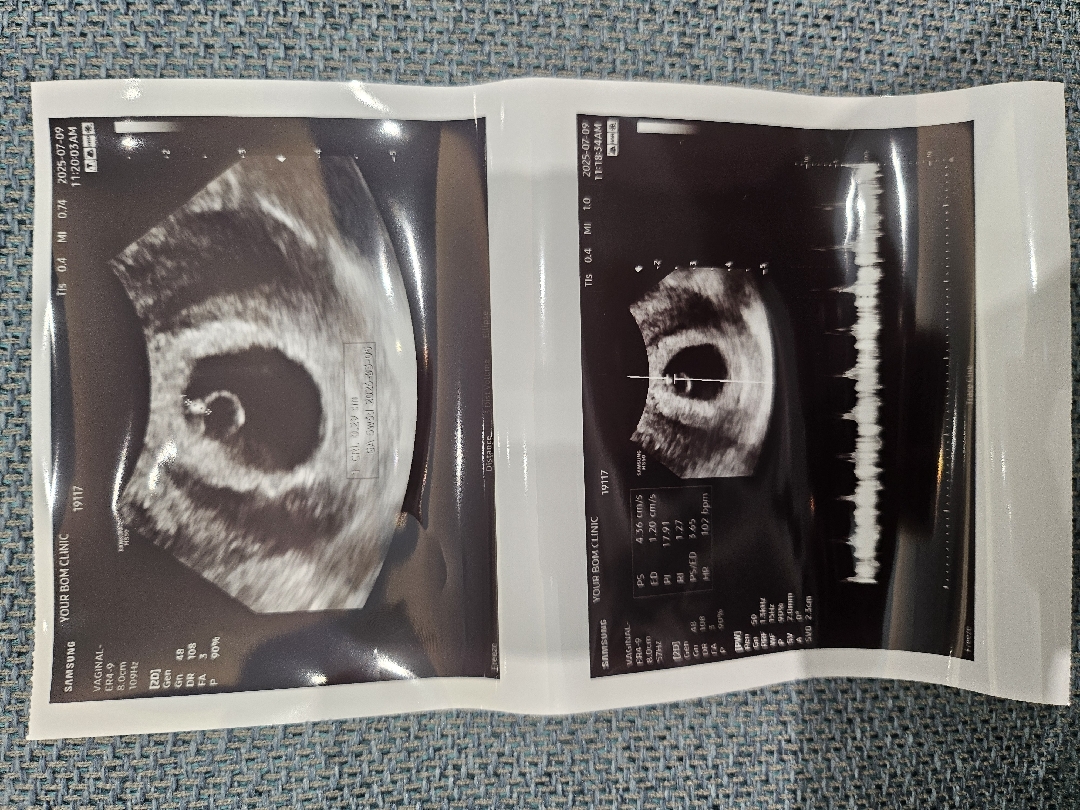

6주 1일차 아기크기

6주1일차 초음파 사진이에요 의사선생님이 아기 심장도 잘뛰고 건강하다고하시는데 아기크기가 0.29mm래요 별말씀 없으셔서 몰랐는데 네이버 주수별 아기크기보니까 보통 0.5이상은 되는거같던데 괜찮은건가요 ? 6주차에 우리아기처럼 작으신분들 계신가요?